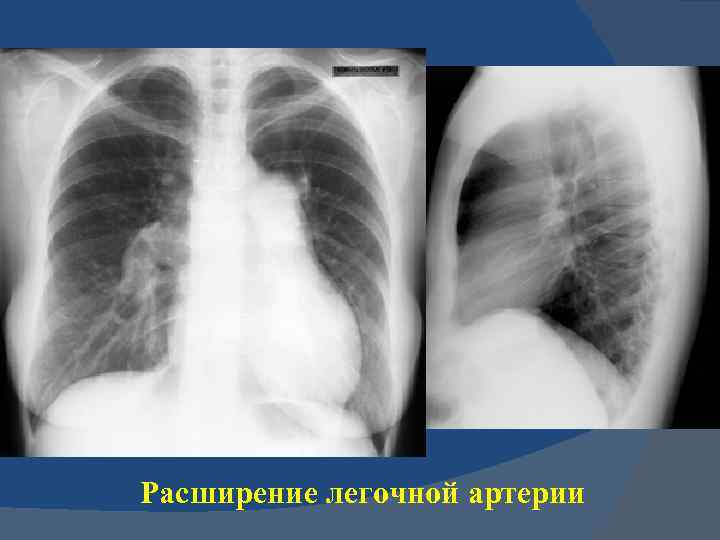

Расширение легочной артерии